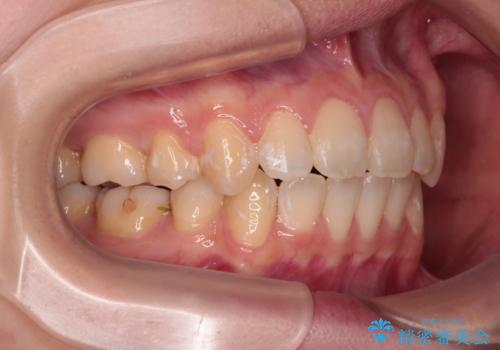

【モニター】口が閉じにくい 抜歯矯正で口元を引っ込める

- 前歯のデコボコや口元の突出感、口の閉じにくさを気にして来院された患者様です。

上下左右第一小臼歯4本を抜歯し、ワイヤー装置にてデコボコを解消しながら口元を引っ込めるよう矯正治療を行うこととしました。